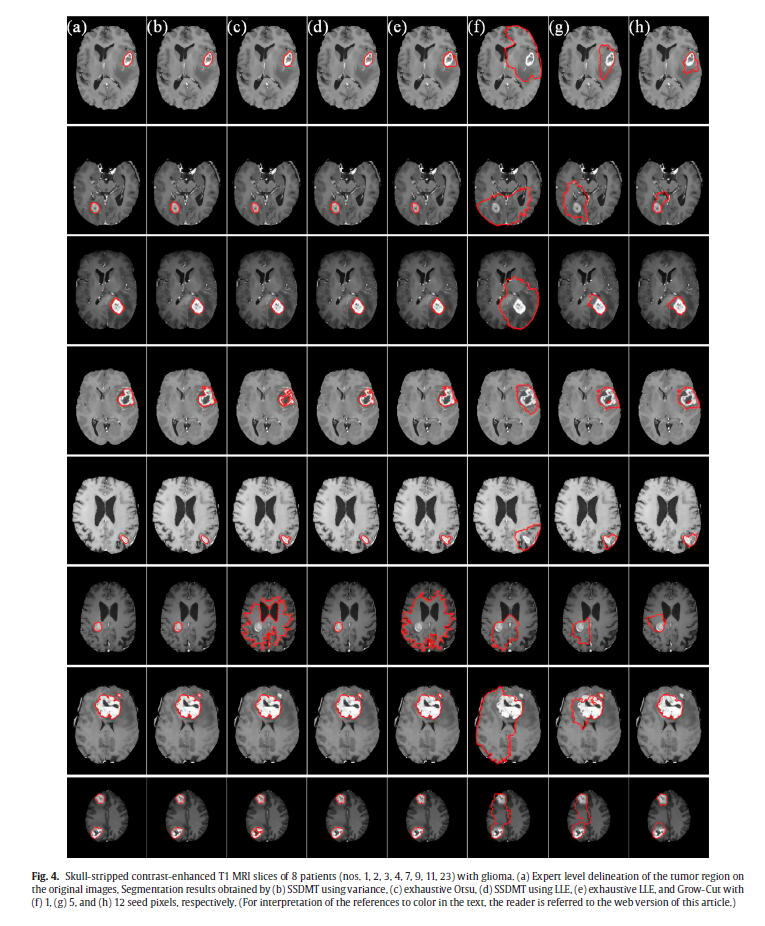

Single Seed Delineation of Brain Tumor using Multi-thresholding, Information Sciences, vol. 330, pp. 88–103, 2016.

©Elsevier (IF: 4.22)(Code)